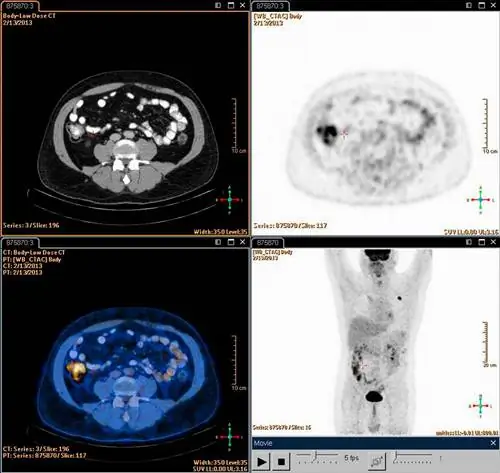

ПЭТ/КТ может помочь обнаружить очаги активной лимфомы Ходжкина в организме.

ПЭТ-сканирование, как правило, более чувствительно, чем КТ, для выявления лимфомы. Например, ПЭТ может выявить заболевание в лимфатических узлах нормального размера и помочь оценить заболевание, которое находится за пределами лимфатических узлов, но не проявляется на КТ. ПЭТ часто комбинируют с КТ, чтобы можно было сравнить области с более высокой радиоактивностью на ПЭТ-сканировании с более подробным изображением этой области на КТ. По сравнению с обычной визуализацией, использование ПЭТ/КТ на исходном уровне может повлиять на стадирование и привести к другому лечению в значительном числе случаев.

ПЭТ/КТ очень хорошо выявляет лимфатические узлы, пораженные лимфомой Ходжкина. Он также хорош для выявления заболеваний костного мозга и других органов. Стадия ЛХ зависит от количества и локализации пораженных лимфатических узлов и других пораженных структур. Исследования показали, что дополнительная выявляющая способность ПЭТ/КТ приводит к тому, что от 10 до 15 процентов пациентов с ЛХ переходят на более продвинутую стадию - более продвинутую, чем стадирование только с помощью КТ. Таким образом, больше пациентов могут получать необходимое им лечение.

Помимо более точного стадирования, ПЭТ/КТ может помочь обнаружить любое заболевание, оставшееся после лечения. Это может быть полезно, например, когда есть остаточная масса или увеличение груди, и неясно, отражает ли это рубцевание или активное заболевание.